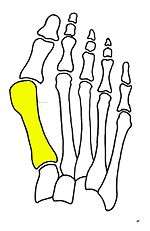

Syndesmosis procedure addresses specifically the two fundamental problems of metatarsus primus varus deformity that gives rise to the bunion deformity. They are leaning and instability of the first metatarsal bone . Syndesmosis procedure uprights the leaning first metatarsal bone with strong binding sutures between it and the second metatarsal bone (Fig. 2) and then also stabilizes it uniquely by creating a fibrous connecting bridge between these two bones (Fig. 3,4). First metatarsal bone can be readily realigned is because by definition of the metatarsus primus varus deformity its first metatarsal is abnormally loose and mobile.